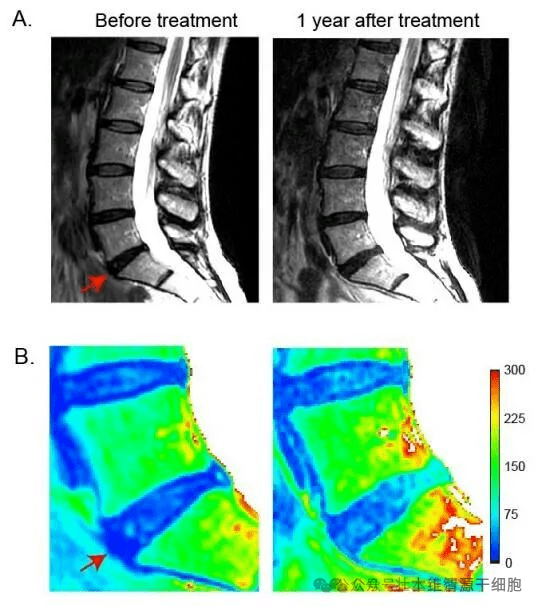

此外,研究者还发现,MSC治疗的患者中,Pfirrmann分级量化的退行性病变得到改善,而对照组却发生了恶化。

△间充质干细胞治疗后MRI变化